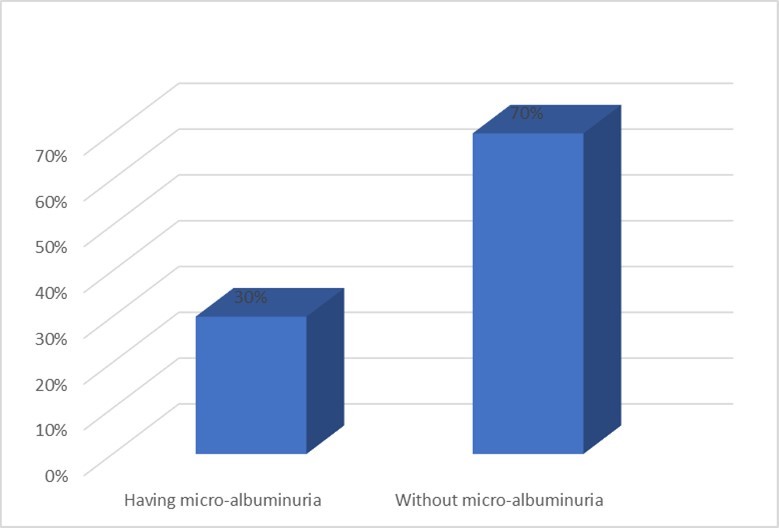

COPD severity was assessed using GOLD guideline. Out of 100 COPD patients, 38% had severe COPD (GOLD stage III). 16 % patients were in mild (Stage I) and 32% patients were in moderate stage (Stage II). The condition was very severe for 14% patients (Stage IV). Of 100 COPD patients. 30% had microalbuminuria. Figure 1

Figure 1.Distribution of COPD patients according to having microalbuminuria (n=100)

Microalbuminuria is an important risk factor for cardiovascular diseases. Microalbuminuria may be seen due to hypoxemia in patients with chronic obstructive pulmonary disease (COPD)22. This study was designed to assess the prevalence of microalbuminuria and its relation with hypoxemia in patients with COPD. Total 100 patients were included. The mean age was 58.16±5.4 years, ranging from 50 to 74 years. This is concordant with the findings of Sujay and Gajanan 23 who found a mean age of 59.67±5.60 years in their study. Majority patients belonged to age group 55 to 60 years (42%), followed by 61 – 65 years (28%). This is slightly different from the findings of Alam et al 24 who reported that majority COPD patients were aged between 60 – 69 years (27.5%) followed by 50 – 59 years (13.6%). This difference may be due to age grouping between the reports. But both the studies confirm that age is a well established risk factor for COPD as increasing prevalence of COPD is noted in higher age groups 79. In this study 82% patients were male and 18% were female. Sujay and Gajanan 23 and Bulcan et al 25 reported a similar high prevalence of male in their study. The high prevalence of male among COPD patients can be linked to high prevalence of tobacco use among male adults in Bangladesh as noted by Khandker et al 26. Majority patients were day labourer (30%), farmer comprised 16% and businessman comprised 16% of study population. Alam et al24 noted that COPD prevalence in Bangladeshi adults were about three times higher in manual workers than non-manual workers. This explains the high prevalence of day labourer and farmers in this study. Slightly more than half of the patients (54%) came from rural area. This was also noted in the study by Alam et al 24 in Bangladesh and Zhong et al 27 in China. Such community variability of COPD can be explained by connecting occupations like farmer living in rural area, use of biomass fuel in the village community and smoking habit among manual workers. Majority patients were illiterate (34%), followed by 26% patients appeared at primary education. This higher prevalence of lower educational qualification in COPD patients was also found in the study by Alam et al24. Majority of the patients came from lower income categories in this study. A similar finding was elicited by Alam et al24 in their study COPD prevalence study among the adult population of Bangladesh. In the present study, 80% of patients were active smokers. Among them, 52% of patients smoked 26 to 35 pack-years. The mean smoking pack-year was 29.62±6.41 years. A similar mean pack-year of 28.91±6.13 was reported by Sujay and Gajanan in their study entitled “Clinical significance of microalbuminuria and hypoxemia in patients with chronic obstructive pulmonary disease” 23. On the other hand Casanova 28 found a high mean pack-year of 58±25 among COPD patients in their study entitled "Microalbuminuria and hypoxemia in patients with chronic obstructive pulmonary disease”. In the present study 38% patients had severe COPD (GOLD stage III), 32% had moderately severe COPD (GOLD stage II), 16% had mild disease (GOLD stage I) and 14% had very severe disease (GOLD stage IV). In contrast Sujay and Gajanan (2) reported 25% GOLD Stage I, 21% Stage II, 20% Stage III, and 34% Stage IV COPD cases in their study. Stage IV cases were higher in their study in comparison to present study. Alam et al (3) in their study entitled “Prevalence and determinants of chronic obstructive pulmonary disease (COPD) in Bangladesh” found that among 13.5% cases of COPD 8% had GOLD stage II disease, 2.7% had stage I disease, 2.3% had stage III disease and 0.6% had Stage IV disease. Their study was community based and depicts the proportion of COPD severity in the community. In contrast the present study as well as the study by Sujay and Gajanan23 was conducted in a hospital setting where advanced cases COPD cases usually get admitted. Microalbuminuria (MAB) was found in 30% patients. This is concordant with other studies: Mehmood and Sofi (8) reported MAB in 20.6% COPD patients and Sujay and Gajanan23 reported MAB in 30% patients. Casanova27 compared presence of MAB in COPD patients and non-COPD smoker controls and found higher prevalence of MAB among COPD patients. In a study by Bulcun et al., 25 it was found that the prevalence of MAB is 39%. In the present study, majority of COPD patients with MAB had GOLD stage of III (40%) and Stage IV (33%), and this association was statistically significant; P = 0.025. In a study by Casanova et al., 28 any association between MAB and spirometric severity of COPD was not observed. Mehmood and Sofi 29 found that COPD patients with MAB had significantly lower levels of FEV1which is similar to finding of present study. In the present study COPD with MAB patients had mean FEV1 % predicted of 37.40±14.48which is significantly lower than those without MAB (59.34±22.78). 26% patients were in hypoxemic status in this study. MAB was significantly more in COPD patients having PaO2 below 70 mm Hg as compared to COPD patients having PaO2 above or equal to 70 mmHg (86.7% vs. 13.3%, respectively, P < 0.001), which indicates COPD patients with MAB were more hypoxemic. In a study by Sujay and Gajanan a Casanova et al. 28 and Mehmood and Sofi, 29 patients with COPD and MAB were more hypoxemic than those without MAB, and it was inversely related to PaO2.